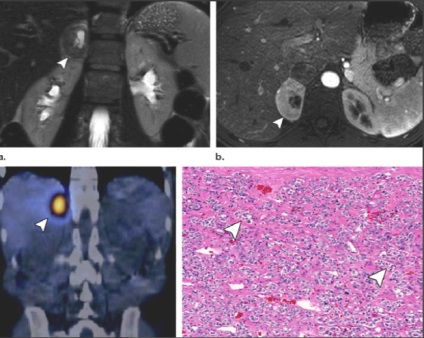

Feocromocitom.

2-8 cazuri la 1 milion. Omul.

F.- este paraganglioma.

F. secreta catecolamină metaboliti + = diagnostic.

Cele mai multe 3-5cm, rotunjite, 35,9 HU ± 9,8 (CT nativ), 10% au calcificări pot fi fibroza, chist, includerea de grăsime, homo- il eterogenă.

De multe ori hipervasculare, dar nu există criterii clare. hiperintensă RMN pe T2VI. Partea f. fără clinica exprimată - accidentală găsi astfel mai mult.

O parte f. cauze ereditare (25-30% din toate f.).

PET / CT 78% sensibilitate (f. Nu mts),

și f. mts cu sensibilitate ≈100%.

De asemenea, PET / CT detectează. pentru adenoamelor și carcinoamelor.

Distinge f. bine și rău este imposibilă fără invazie a structurilor din jur și mts

(În regional l / y, rinichi, ficat, os).

F. variabilă - „imagine cameleon“. Se recomandă să se includă f. în leziunile DD cu densitate scăzută, washout HF rapidă, leziuni chistice cu componenta dominantă, în funcție de parametrii clinici și de laborator.